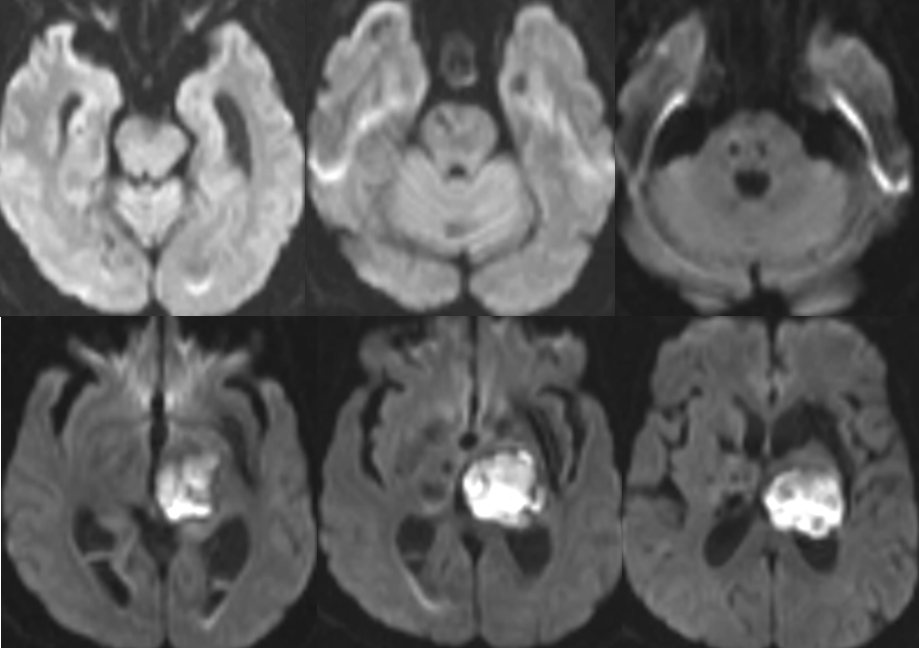

脑干梗塞?

2014-11-27 MRI

渗透性脱髓鞘综合征?

渗透性脱髓鞘综合征(osmotic demyelination syndrome,ODS)

是一种少见的急性非炎性中枢脱髓鞘性疾病,主要是由于慢性低钠血症时脑细胞已经适应了一种低渗状态,此时一旦给予迅速补钠,血浆渗透压迅速升高造成脑组织脱水而继发脱髓鞘。

分为脑桥中央髓鞘溶解症(central pontine myelinolysis, CPM),脑桥外髓鞘溶解症(extrapontine myelinolysis, EPM)。

CPM表现为四肢瘫和不同程度的脑干功能障碍,如假性延髓麻痹,偶有闭锁综合征、缄默症。EPM主要表现为运动障碍、肌张力障碍、帕金森综合征等,仅出现小脑体征者罕见。

影像学特征

CT表现为脑桥中央或脑桥外病灶处的低密度影。

MRI能更好地反映病灶的数量和程度。早期可无异常,出现症状后1周DWI上可发现高信号。急性期表现为对称的T1WI低信号,亚急性期可能是由于内皮细胞受损所致的微出血而显示T2WI高信号。FLAIR显示病灶高信号更清楚,能更好地显示临近脑脊液的病灶,比如大脑皮质,应作为常规检查。也有一些报道发现皮质层及皮质下T1高信号,有的钆增强被强化,有的不被强化。脑MRI对本病具有十分重要的诊断意义,大约在发病2~3周时异常信号最为明显,所以结合病史及临床表现如果考虑ODS的诊断,在MRI检查正常的情况下,在出现症状后10~14天复查MRI是十分重要和必要的。